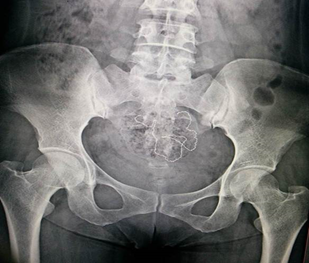

Особая категория инородных тел в организме человекам – это инородные тела, оставленные в результате хирургических вмешательств. Это относительно редкое осложнение. До 50% всех инородных тел составляют забытые хирургические тампоны, марлевые салфетки дренажные трубки, фрагменты катетеров, хирургические инструменты. Чаще всего инородные тела остаются после полостных операций, реже – после лапароскопических, эндоскопических, чрескожных. Наиболее распространенными локализациями ИТ являются брюшная полость, полость таза, также описаны случаи их нахождения в грудной, плевральной, перикардиальной полостях, забрюшинном пространстве, полости черепа, мягких тканях.

Диагностика рентгенпозитивных инородных тел успешно проводится с помощью традиционной рентгенографии и ультразвукового исследования (УЗИ) .

Рентген -диагностика.

Выявляется:

- дополнительная тень в зоне интереса;

Метод выбора для выявления госсипибомы - КТ. В раннем послеоперационном периоде госсипибома наиболее достоверно диагностируется при визуализации округлого образования с губчатой внутренней структурой, с множественными пузырьками газа в структуре. При в/в контрастировании визуализируется тонкое периферическое кольцо контрастного усиления, соответствующее гранулематозному воспалению вокруг инородного тела. В позднем послеоперационном периоде госсипибома может утратить губчатую структуру и КТ-картина может быть сходна с ограниченным скоплением жидкости или с абсцессом. В отдаленном послеоперационном периоде госсипибому следует дифференцировать с новообразованиями, при этом отмечается отсутствие достоверного накопления контрастного вещества как в центральной зоне, так и стенке госсипибомы. В позднем и отдалённом постоперационном периоде также возможна кальцификация стенок госсипибомы.

- использование интраоперационной рентгенографии на передвижных рентгеновских аппаратах в сомнительных случаях до закрытия операционной раны.

- целесообразно использование хирургического материала рентгеноконтрастными метками, что облегчает их обнаружение при лучевой диагностике.